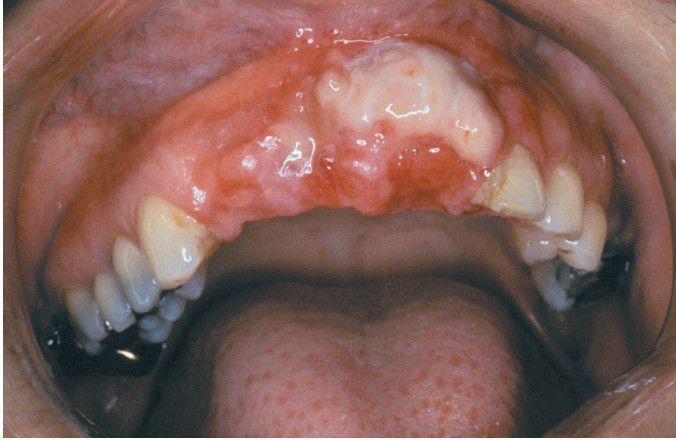

Leiomyosarcoma

Ulcerated mass of the anterior maxillary alveolar ridge.

Ulcer

Mass